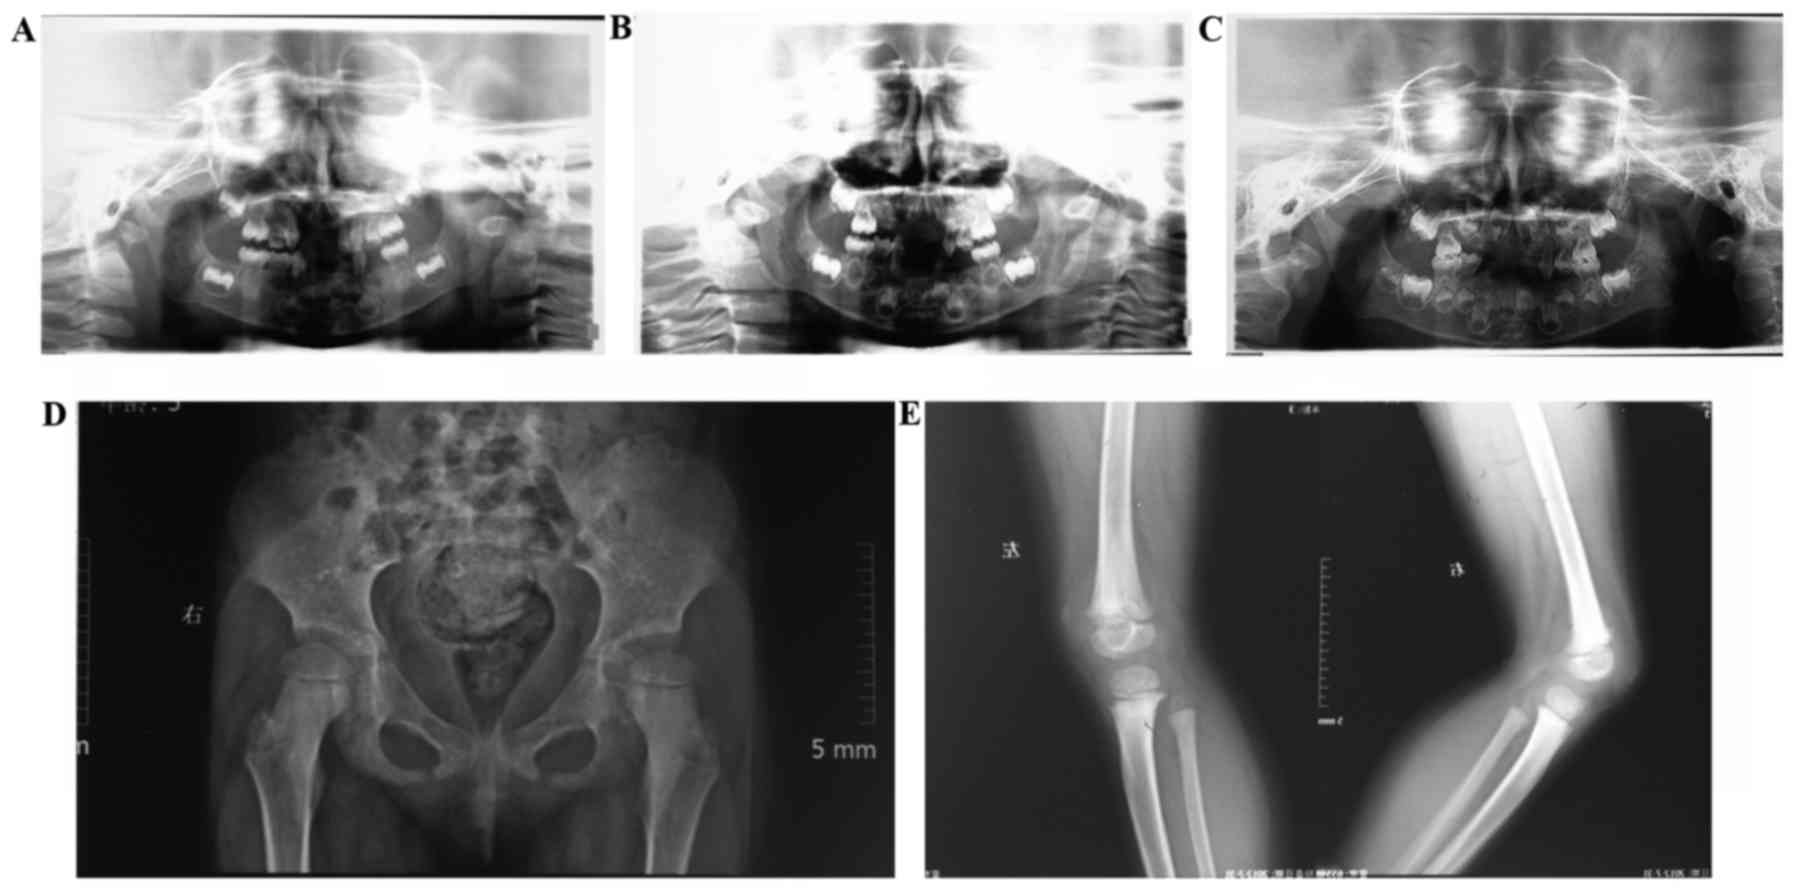

A physical examination demonstrated that the body weight and height of the patient was just above the norm. She had a waddling gait without limb or skin abnormalities. Extensive premature loss of deciduous teeth was observed, with only 55, 63, 64, 65, 75, 84 and 85 remaining (Fig. 2A). In addition, constricted neck and denudation of dentin on the occlusal surface was observed in several teeth (Fig. 2B). Furthermore, although abnormal mobility was detected, the patient had a good oral hygiene, demonstrating no sign of attachment loss. Panoramic radiographs demonstrated malformed deciduous teeth without congenital loss of permanent teeth. No considerable alveolar bone resorption was observed during the 3-year follow-up (Fig. 3A-C).

Imaging examination. (A-C) Panoramic radiographs from the past 3 years demonstrated no considerable alveolar bone resorption. X-ray films revealed (D) a slight dislocation of the hip and (E) mild osteodystrophy in the knees and rough epiphyseal plate.

Slight dislocation of the hip and disrupted Shenton's lines were observed with mild osteodystrophy in the knee. In addition, a wide epiphyseal plate with rough surface was observed (Fig. 3D and E). Bone mineral densitometry velocity of sound was 3698 m/s, and the Z-value was 1.96 m with a relative risk of fracture of 1.000.